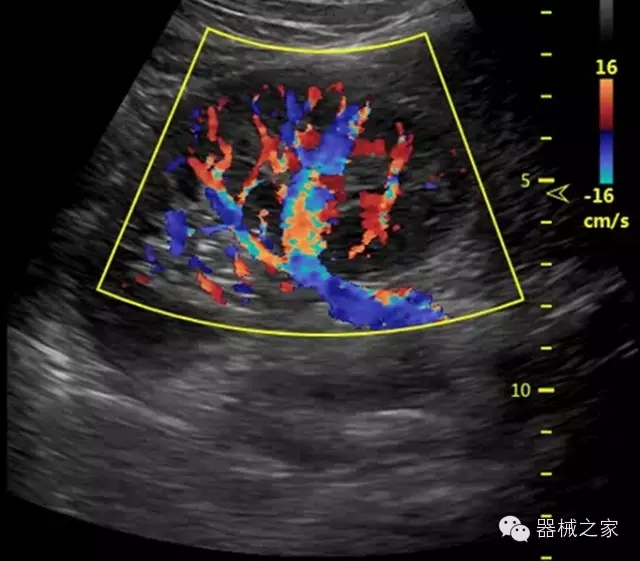

臨床圖片賞析

·智能微血流成像技術(shù):智能微血流捕捉技術(shù)可以提取出隱藏在背景噪聲中的弱血流信號(hào),大大提高低速血流的敏感性;